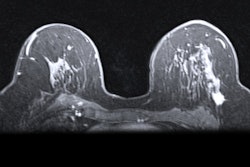

On the other hand, contrast-enhanced spectral mammography can be performed with conventional mammography equipment and an iodinated contrast agent. CESM can help spot potentially malignant tissue by acquiring images at different x-ray energy levels and demonstrating differences in the response of different kinds of tissue.

In the new study, the team wanted to compare the clinical efficacy of contrast-enhanced spectral mammography and MRI as supplements to mammography and ultrasound to identify the extent of disease in women with newly diagnosed invasive breast cancer.